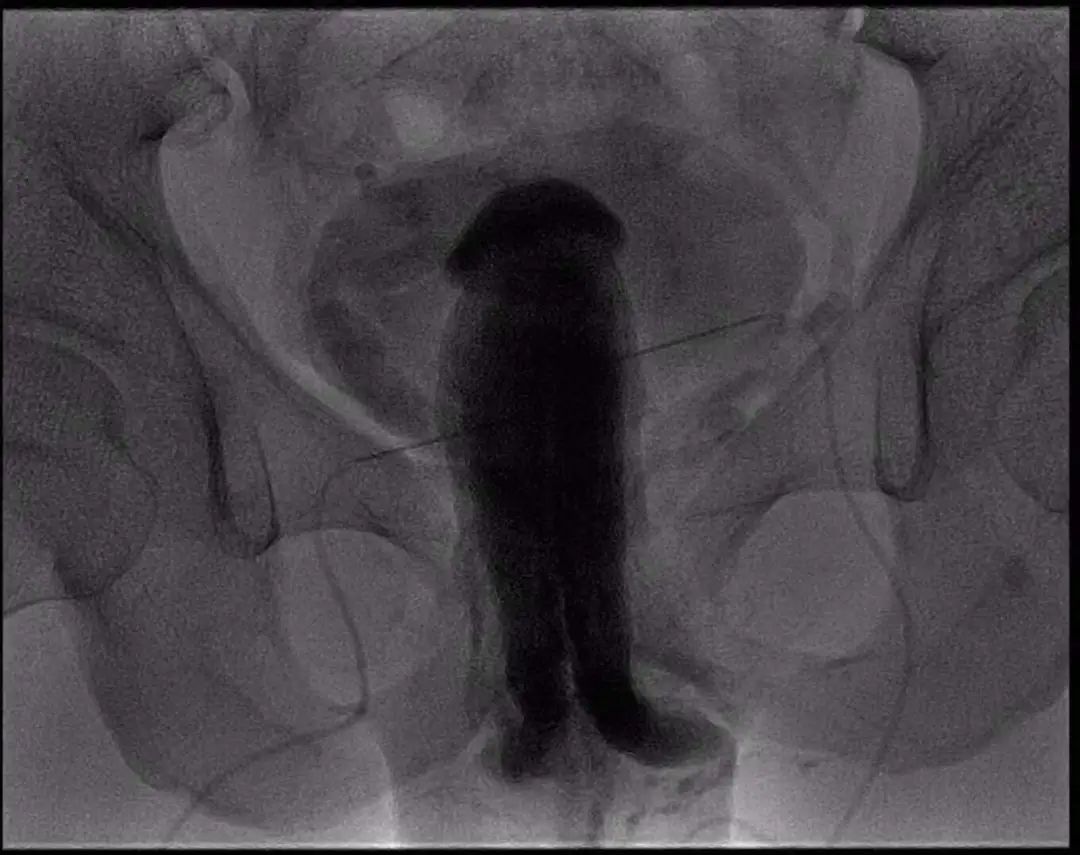

4.阴茎海绵体测压及造影(DynamicInfusion Cavernosometry and Cavernosography ; DICC)

DICC对于静脉型ED有很好的诊断价值; DICC可以指导静脉型ED的临床分类,为下一步治疗提供帮助。被认为是诊断静脉性ED金标准,能为静脉性ED的早发现、早诊断、早治疗提供依据。

适应症

c主诉阴茎勃起困难、硬度不佳或勃起后未射精的情况下出现很快疲软;

C同时行彩色多普勒双功能超声检查(CDDU)显示:阴茎双侧的海绵体动脉PSV>25cm/S,EDV> 5.0cm/S,怀疑存在静脉漏型勃起功能障碍;

C这些患者均通过主诉及病史,IEF-5评分,阴茎海绵体注射试验(ICI)筛选阴性。